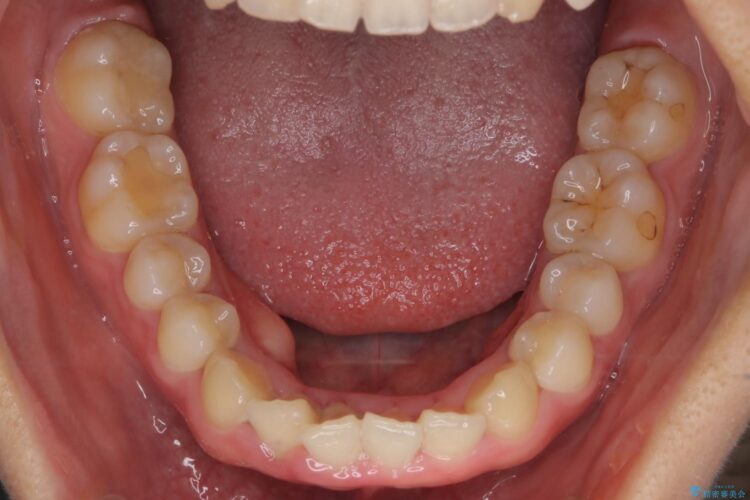

下の前歯のガタつきと正中のズレが気になるとご来院された患者様です。

軽度のガタつきだあったのと、かみ合わせがやや深かったため、インビザラインで治療を行うこととしました。

IPR(歯と歯の間を削る処置)と歯列拡大をすることでガタつきをとります。

前歯のガタつきを改善するのに時間がかかりましたが、ガタつきもかみ合わせも綺麗になりました。